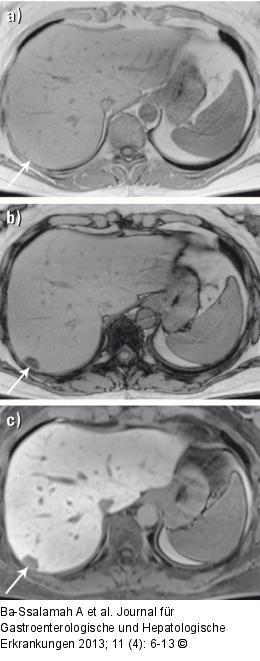

Abbildung 3a-c: MRT-Diagnostik MRT-Erscheinungsbild und MRT-KM-Anfärbeverhalten des steatotischen Adenoms. (a) In dem T1-gewichteten Bild In-Phase ist das kleine steatotische Adenom im Segment 7 (Pfeil) aufgrund des Fettgehalts hyperintens (= hell). (b) In dem T1-gewichteten Bild Opposed-Phase ist das kleine steatotische Adenom im Segment 7 (Pfeil) typischerweise hypointens (= dunkel) geworden, der Beweis für die Fetthältigkeit des Läsion. (c) 20 Minuten nach Gabe von Gadoxetat zeigt das kleine steatotische Adenom im Segment 7 (Pfeil) ein deutliches Auswaschen. Diese MRT-Merkmale erlauben die sichere Diagnose eines kleinen steatotischen Adenoms und indizieren eine Verlaufskontrolle. |

MRT-Erscheinungsbild und MRT-KM-Anfärbeverhalten des steatotischen Adenoms. (a) In dem T1-gewichteten Bild In-Phase ist das kleine steatotische Adenom im Segment 7 (Pfeil) aufgrund des Fettgehalts hyperintens (= hell). (b) In dem T1-gewichteten Bild Opposed-Phase ist das kleine steatotische Adenom im Segment 7 (Pfeil) typischerweise hypointens (= dunkel) geworden, der Beweis für die Fetthältigkeit des Läsion. (c) 20 Minuten nach Gabe von Gadoxetat zeigt das kleine steatotische Adenom im Segment 7 (Pfeil) ein deutliches Auswaschen. Diese MRT-Merkmale erlauben die sichere Diagnose eines kleinen steatotischen Adenoms und indizieren eine Verlaufskontrolle. |